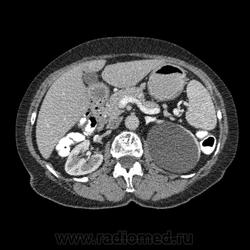

Впечатление, что дуля эта вне головки п.ж., интрамурально в луковице, что ли... тогда возможно GIST, но надо дайком. Утолщение подслизистой в антральном отделе желудка, не удается проследить переход от желудка к 12-перстной((. Внутрипросветно/внутристеночно - не разобрать. 1 фаза?

Клинику! Есть ли признаки высокой тонкокишечной непроходимости, что при ФЭГДС в 12-перстной - туда удалось пройти или нет? ААА! Одни вопросы))))

В-общем, варианты такие без дайкомов: пролапс слизистой в 12перстную, безоар, внутрипросветный дивертикул, гастроинтерстинальная опухоль. И большие сомнения, что это в головке п.ж. - оно отделено от неё тонким слоем жировой клетчатки

Фаз было 3. Видео не выставлял прошлый раз пришел ответ из сайта что видео не работает на сайте Идет накопление контраста в нативе в центре +2+4 по периферии +32+34 .в артериальную +20 и +65 +70 соответственно.

Что оно копит - бог с ним... если это пролапс слизистой, то суммация стенок. Безоар бы не копил. Напрягает отек слизистой в антрале... Это должно быть скорее внутри просвета кишки, т.к. оттесняет газ в 12-перстной на периферию. Без дайкомов больше ничем не могу, извините. Подождём мнения коллег.

Как мне видится - пролапс слизистой желудка в 12-перстную. А мнения коллег что-то нетути...

А что растет из левой почки? Может оно же и желудок сдавливает?

Это расширение всей 12- перстной кишки (стаз).